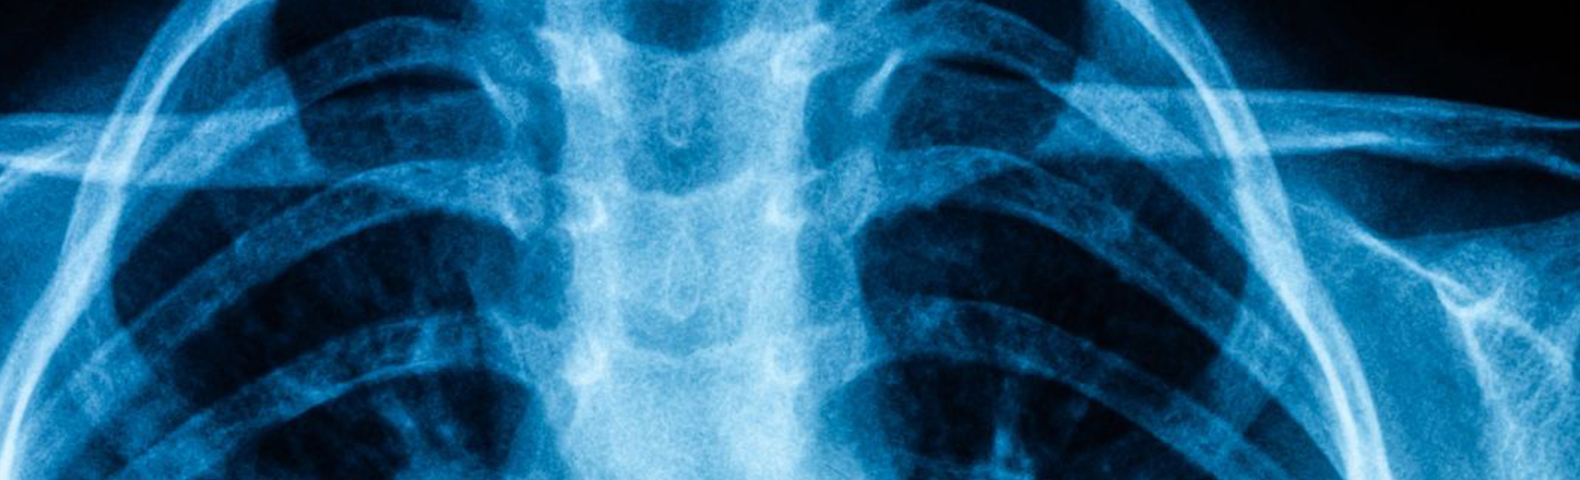

Thoracic Outlet Syndrome (TOS) might sound complex, but understanding it is crucial for effective management. TOS occurs when the nerves or blood vessels between your collarbone and first rib become compressed. This narrow space, known as the thoracic outlet, houses key anatomical structures: the brachial plexus (a network of nerves controlling the shoulder, arm, and hand), the subclavian artery, and the subclavian vein. Compression in this area can lead to a range of symptoms that disrupt daily activities.